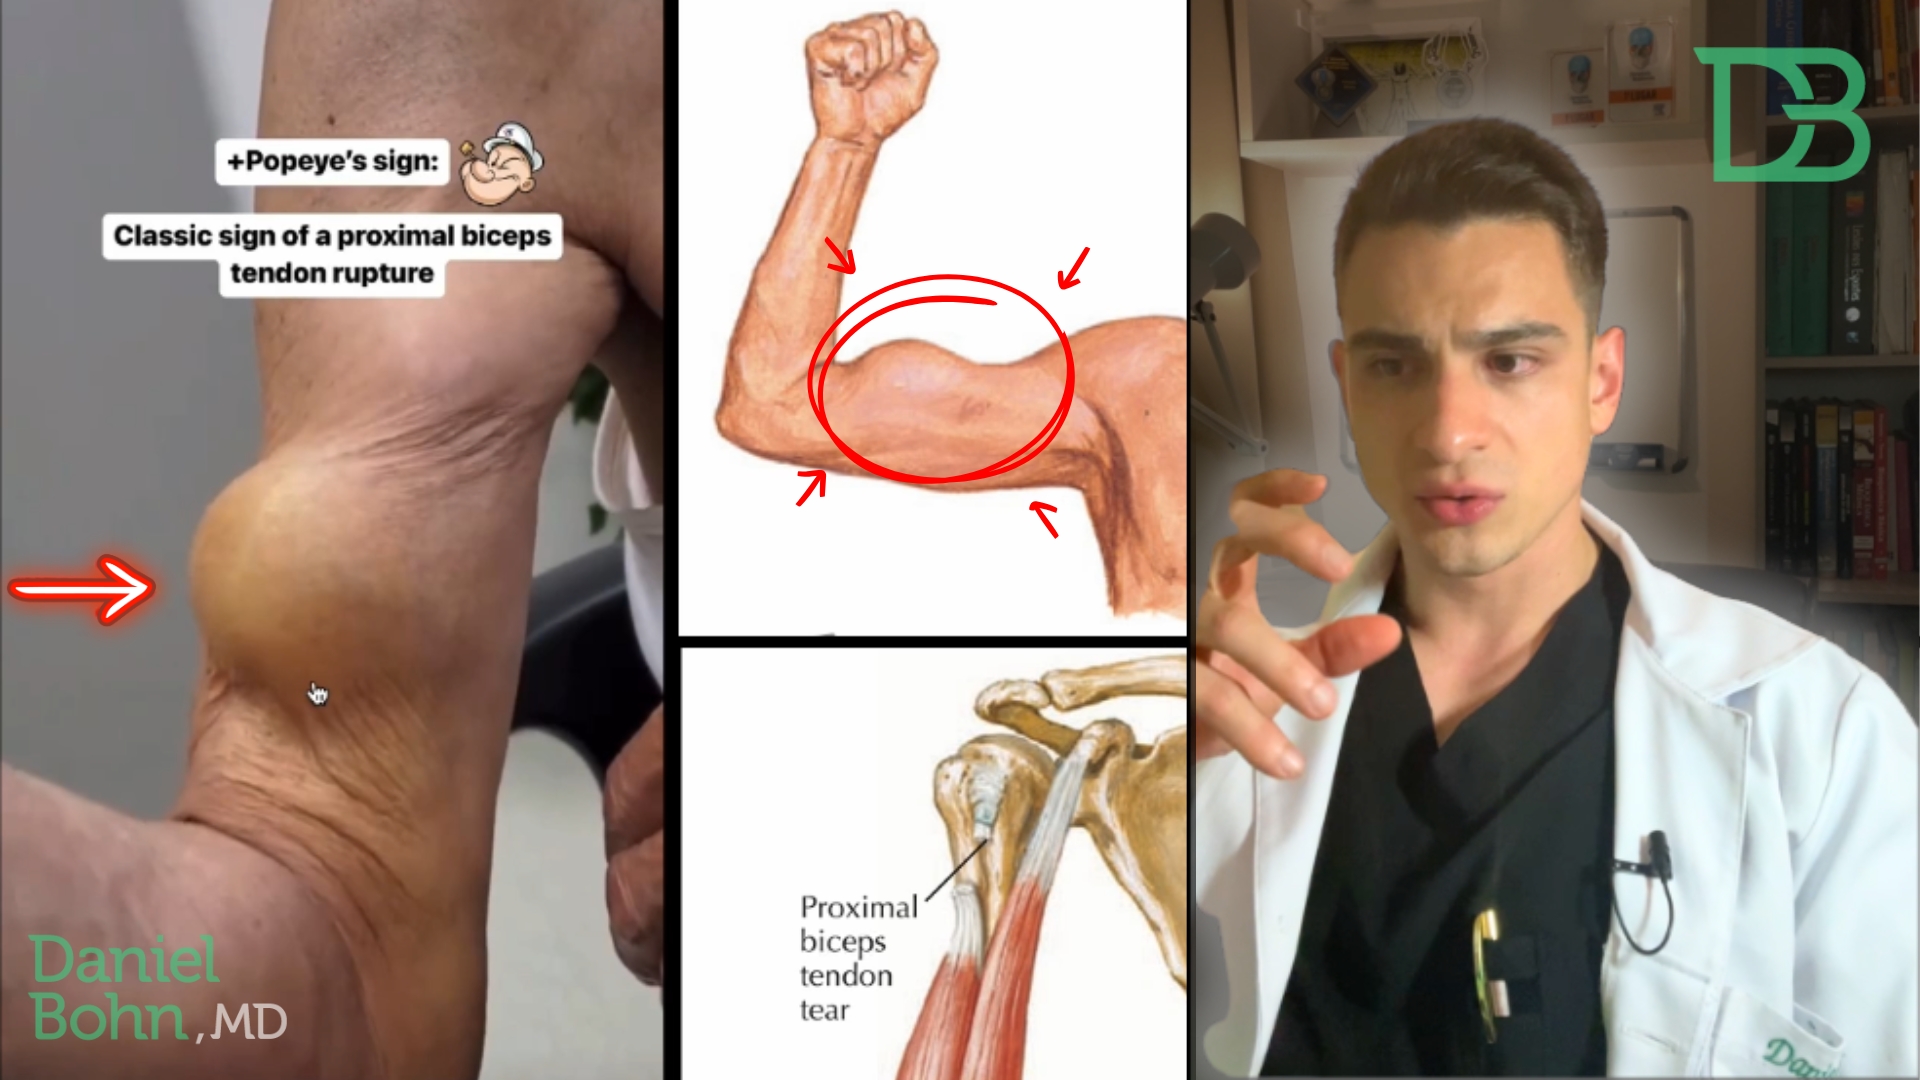

Veja a apresentação Clássica no vídeo abaixo: A dor na parte frontal do ombro, que muitas vezes se estende para o braço, …